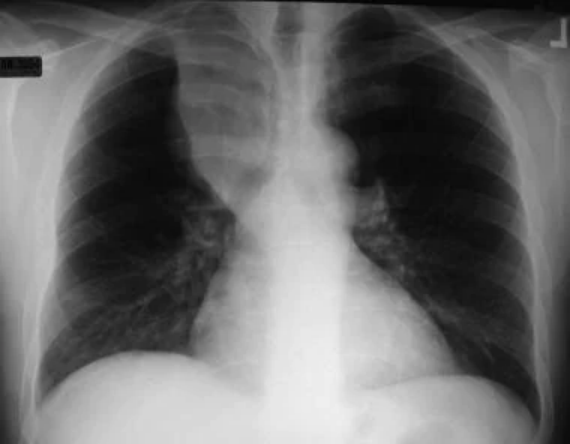

非小细胞肺癌。左下叶非小细胞癌继发的左胸腔积液和容量减少。对胸腔积液取样,发现是恶性的。因此,病变无法手术。